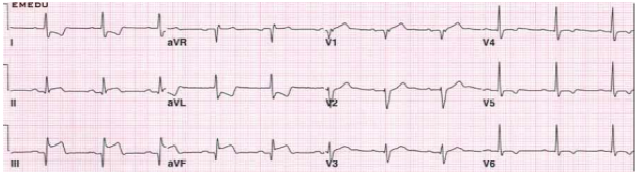

Edileuza, 64 anos, tabagista e diabética, procura serviço de pronto atendimento com dor precordial há 2 horas e PA

= 149x96 mmHg. A paciente realiza eletrocardiograma, conforme imagem a seguir:

Após a realização do eletrocardiograma, o plantonista institui algumas condutas terapêuticas. Porém, após a utilização de uma das medicações, o quadro de Edileuza evolui para hipotensão acentuada, mal-estar generalizado e sintomas de baixo débito, sem rash cutâneo ou angioedema. Qual medicação poderia justificar o quadro dessa paciente?

Após a realização do eletrocardiograma, o plantonista institui algumas condutas terapêuticas. Porém, após a utilização de uma das medicações, o quadro de Edileuza evolui para hipotensão acentuada, mal-estar generalizado e sintomas de baixo débito, sem rash cutâneo ou angioedema. Qual medicação poderia justificar o quadro dessa paciente?